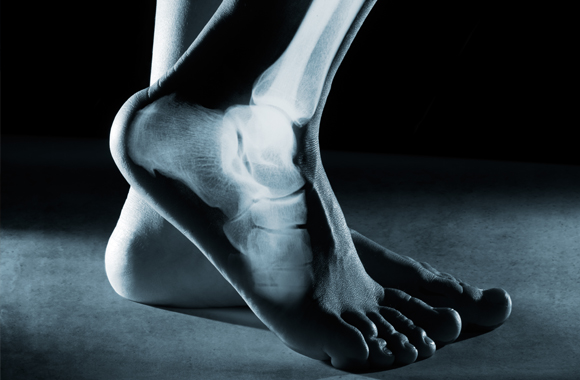

Foot and ankle fractures are often diagnosed through diagnostic imaging, like X-rays. X-rays can clearly illustrate the outline of the bones inside our body to determine the location and severity of the damage within the region. If an injury is more severe or if the type of fracture is unclear, further testing with an MRI or CT scan may be necessary to determine the full extent of the break.